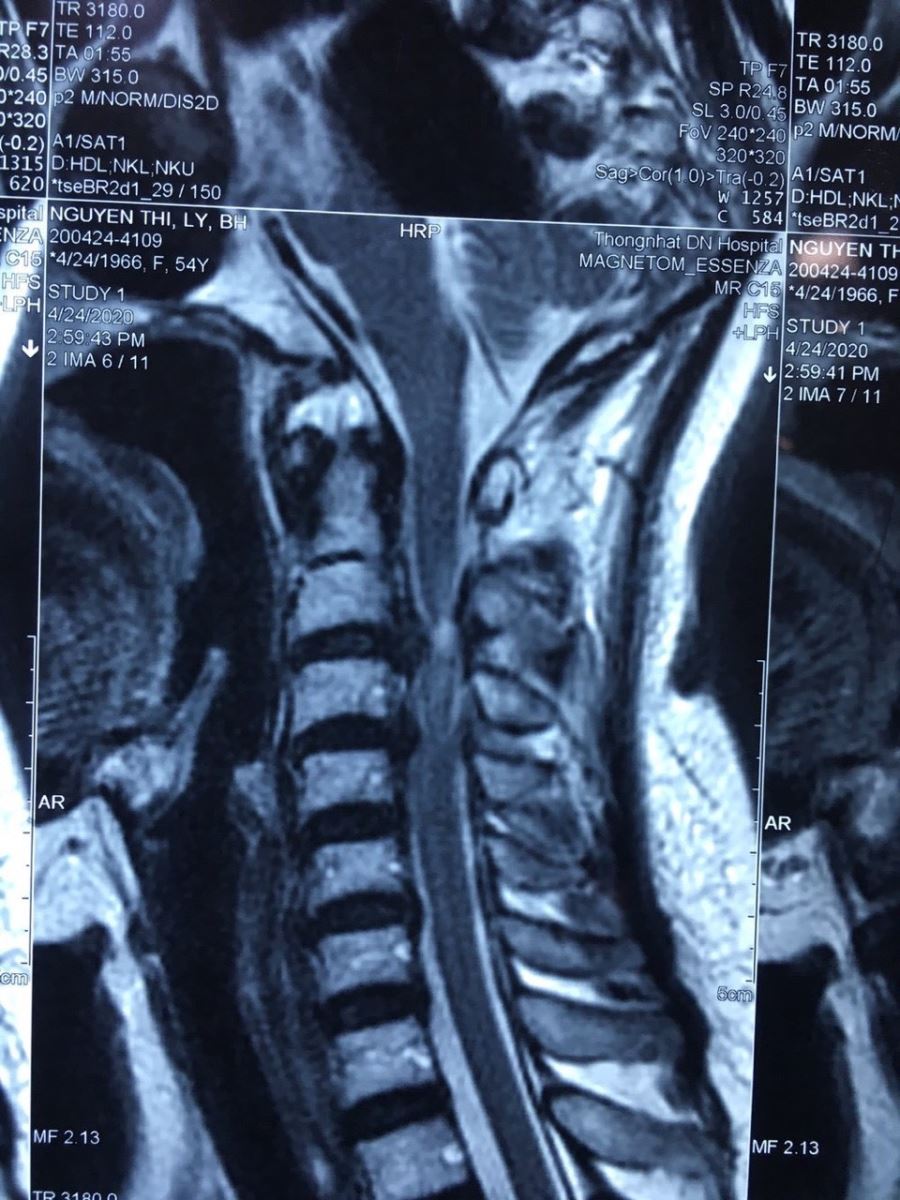

Bệnh nhân nữ 54 tuổi, bị thoát vị đĩa đệm C2C3, C3C4 gây đau tê vùng cổ lan lên gáy và lan xuống hai tay, vận động hạn chế do đau ảnh hưởng sinh hoạt, cầm đũa muỗng ăn cơm đối với bệnh nhân cũng trở nên khó khăn. |

Hình chụp cột sống sau phẫu thuật thay đĩa đệm nhân tạo C2C3, C3C4 giải phóng thần kinh chèn ép; Bệnh nhân sau mổ hết tê tay, giảm đau, hai tay vận động linh hoạt như trước, giúp nâng cao chất lượng cuộc sống. |